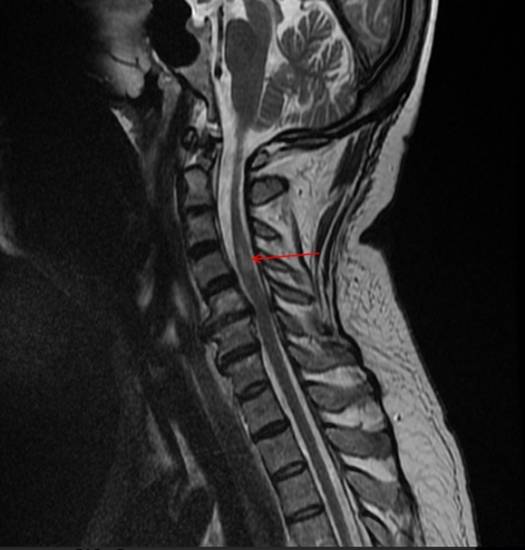

На МР-томограмме представлен остеохондроз шейного отдела позвоночника с формированием задней грыжи диска между пятым и шестым шейными позвонками, сдавливающий позвоночную артерию: стрелкой указан сформировавшийся в итоге участок инфаркта (нарушения процесса кровообращения) спинного мозга